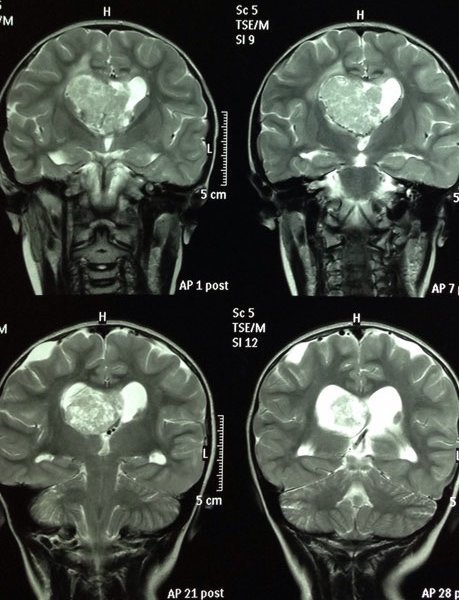

ESCLEROSIS TUBEROSA